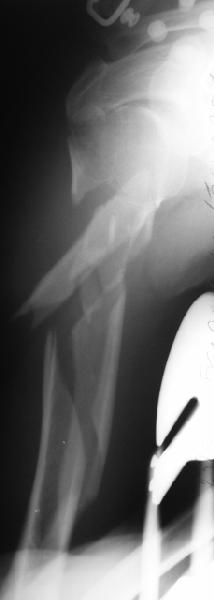

Отправитель: Alexander Chelnokov 05 Октябрь 2003, 13:41

1

2

Well, to date he is still on abduction splint with traction applied to a wire placed through the olecranon. Images attached. The acetabulum

was ORIFed. The humerus is still discussing...

The views you now show demonstrate an extra articular fracture with good alignment on the AP, and some displacement on the lateral.

This should be able to be managed with adjustment of the traction.

Ilizarov is probably the best fixation if you decide to do so. However, it will heal with nonoperative treatment, with painless, reasonable

function. Even if it does not heal primarily, the pieces will heal enough to become a single level problem, readily solved with compression

plating. Jim Carr